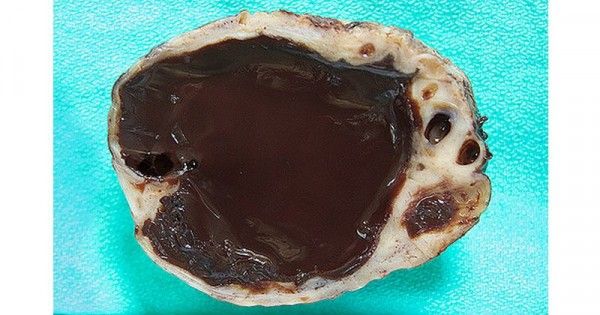

5 Fakta Kista Coklat yang Harus Diketahui | Popmama.com

5 Fakta Kista Coklat yang Harus Diketahui | Popmama.com

5 Fakta Kista Coklat yang Harus Diketahui | Popmama.com

5 Fakta Kista Coklat yang Harus Diketahui | Popmama.com

5 Fakta Kista Coklat yang Harus Diketahui | Popmama.com

5 Fakta Kista Coklat yang Harus Diketahui | Popmama.com